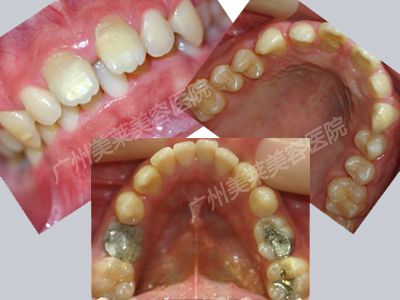

牙齒問題:上牙間隙過大,下牙部分擁擠,爛牙

治療前林偉口腔

治療原因:“因為上牙縫隙很大,然后爛牙容易有口臭,不知道什么時候開始就下意識地說話或者笑,都不露齒,大學天聚餐就被同學說,像個娘們一樣笑不露齒的……”